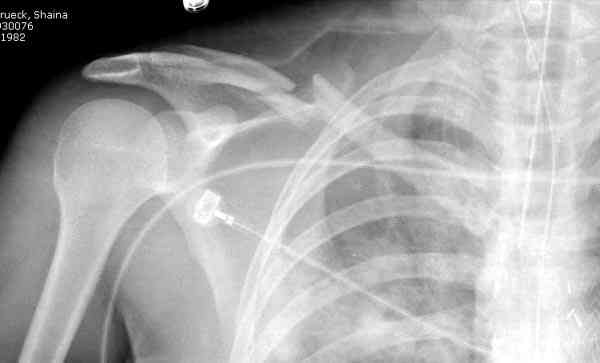

Второй случай тоже недавно оперирован по поводу

ложного сустава, в марте травма, через 4.5 половиной

операция..

Описанный случай это больная моего партнера, мы недавно случай разбирали на нашей конференции (Morbidity and Mortality Conference аналог клинического разбора)

Выставлен как пример, к чему может привести

неудачно выбранный фиксатор.

Больные иногда пропадают из нашего поле зрения, ту больную неудачно оперировал в нашем городе специалист по спортивной медицине. Он же направил к нам после удаления фиксатора.